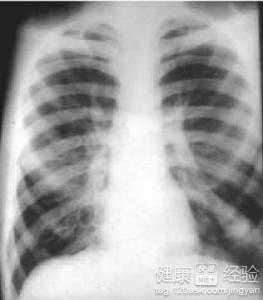

肺源性心髒病的患者在平時的生活當中,一定要引起注意要調理好自己的心理方面,要積極的去進行治療。因為肺源性心髒病的出現患者的心態是非常重要的,這個時候患者會變得過於憂郁,也會提不起精神來,所以在這種情況下,我們更應該去注意患者的心理方面的活動,要改善患者的生活環境。我們下面來具體了解一下肺源性心髒病的護理措施。

肺源性心髒病護理措施有哪些